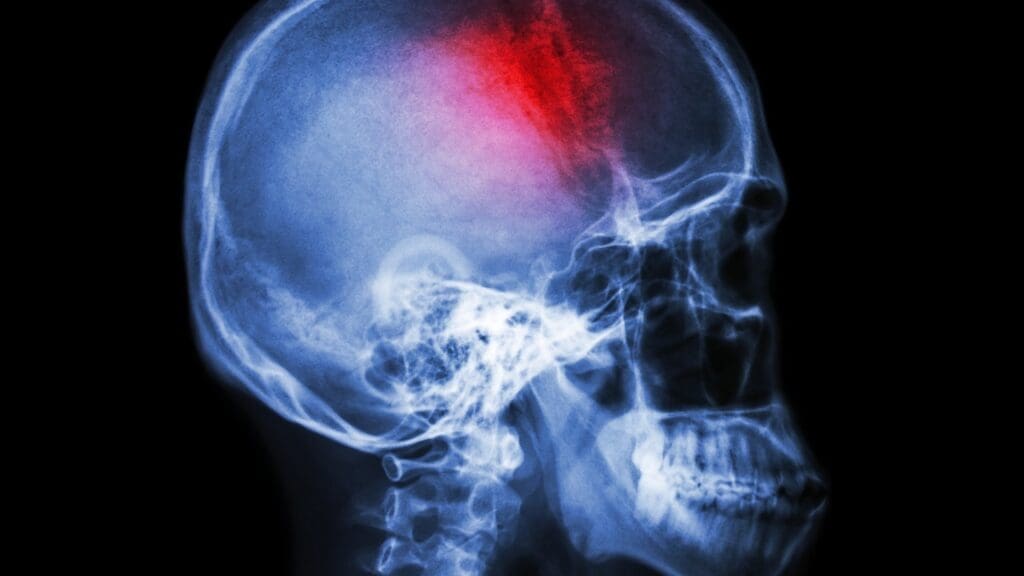

Imaging Techniques for Identifying Calcified Tumors

Imaging is key in finding calcified meningiomas. We mainly use MRI (Magnetic Resonance Imaging) and CT (Computed Tomography) scans. MRI shows soft tissue details, and CT scans spot calcifications.

Distinguishing Features on Brain Scans

On brain scans, calcified meningiomas show clear signs. They appear as dense spots on CT scans. MRI helps see how the tumor affects nearby areas and if there’s swelling.